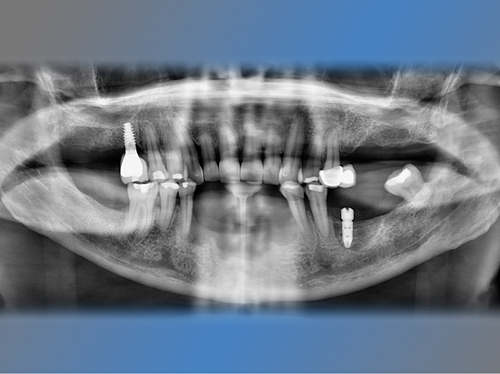

Joaquín vino a la clínica dental en Valencia IDIM a causa del fracaso de unos implantes antiguos.

La infección de estos implantes había causado una pérdida de hueso importante en la zona anterior de su mandíbula.

Se optó por colocar 5 nuevos implantes al mismo tiempo que se regeneraba su mandíbula con un injerto óseo. Se utilizaron 4 de estos implantes para ponerle una prótesis fija provisional al cabo de 24 horas (carga inmediata).